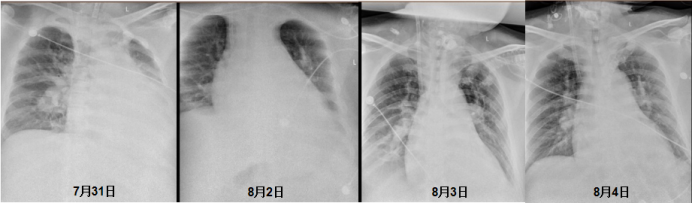

图片

患者X线胸片

(2)呼吸支持:胸部X线片变化及气管镜复查提示肺水肿加重,明确病原学后给予抗感染、甲强龙40mg q12h抗炎,加强补胶体利尿减轻肺水肿。肺复张及高PEEP 20 cmH2O改善氧合,因设备问题未能监测跨肺压。抬高床头改善膈肌功能,降低镇痛镇静药物,恢复自主呼吸,患者氧合改善明显。ECMO上机第6天撤除ECMO,入院第8天撤除呼吸机改为高流量吸氧,吸氧浓度40%。在镇痛镇静药物减量过程中出现烦躁,考虑ICU谵妄,给予奥氮平及右美托咪定短暂应用后好转。